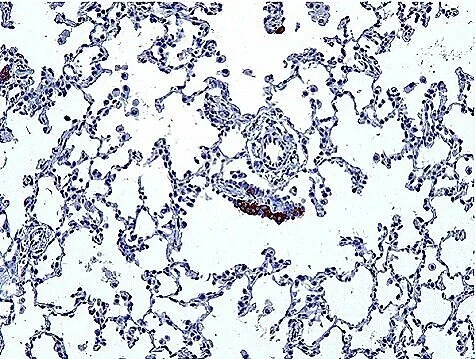

Pulmonary neuroendocrine cells (PNECs) are most prominent during fetal and early postnatal lung development. They express a variety of neuropeptides, neurotransmitters, and hormones, including gastrin-releasing peptide, calcitonin, and calcitonin gene-related peptide.  We recently identified the remarkable diversity of NE signals (Kuo et al, 2022). PNECs cluster at airway branchpoints to form structures called neuroepithelial bodies (NEBs), which are uniquely organized, innervated within the airway epithelium.

To investigate the onset of these diseases linked to improper neuroendocrine cell development, we study how these clusters form, their typical locations in humans, and the signals they emit. Our research employs in vivo genetic cell labeling, high-resolution live imaging, and single-cell transcriptomics, using both animal models and human tissue samples.

Molecular interrogation and understanding of neuroendocrine (NE) cell diversity and function in the lung has been historically limited by their scarcity; they constitute approximately 0.01% of human lung cells. To address this challenge, we employed single-cell RNA sequencing to isolate and profile hundreds of pulmonary neuroendocrine cells, initially in mice and later extending to human lung tissue.